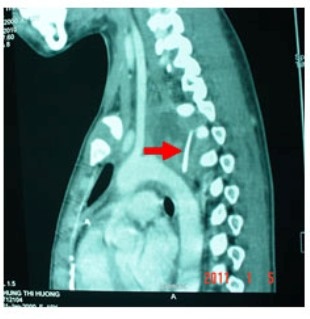

Mảnh xương gà sau khi đâm thủng thực quản đã nằm sát cột sống của bé

Tại đây qua kết quả CT scan cho thấy ngực của cháu có dị vật cản quang dạng xương dài 28mm. Dị vật đã đâm thủng thực quản và động mạch chủ tạo thành một túi phình lớn xô lệch khí quản và thực quản. Nhận thấy đây là một trường hợp rất nguy hiểm nên bác sĩ bệnh viện địa phương chuyển bé lên bệnh viện Nhi Đồng 1.

Theo nhận định của bác sĩ đây là một trường hợp đặc biệt nguy hiểm vì sau khi xuyên qua thực quản mảnh xương tiếp tục xuyên ra phía sau nằm cạnh cột sống tạo nên túi giả phình động mạch. Nếu túi phình này vỡ ra bệnh nhân sẽ đột tử tại chỗ.